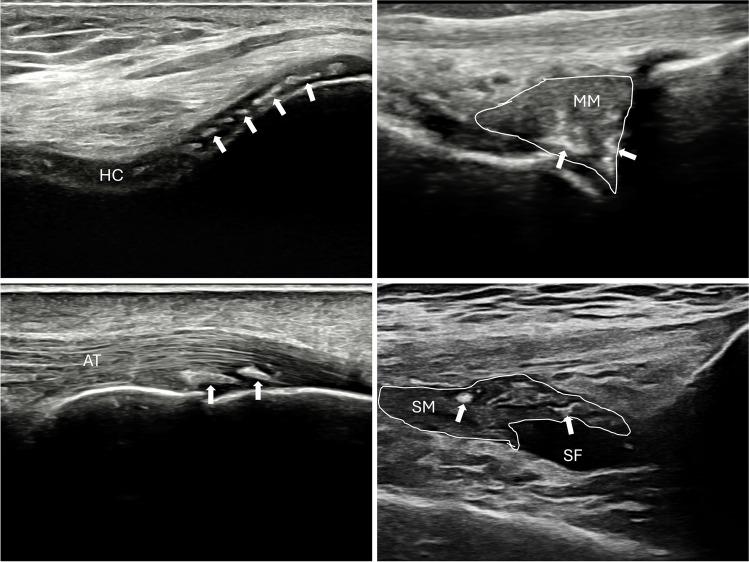

Recent years have seen significant advances in CPPD research, particularly in the clinical field with the development of the 2023 ACR/EULAR classification criteria for CPPD disease, and in imaging with the introduction of the OMERACT ultrasonographic definitions and scoring system. However, progress in basic research has been slower. New laboratory approaches, such as Raman spectroscopy and omics sciences, offer promising insights that may help piece together the puzzle of CPPD. CPPD is a common yet understudied condition. As the population ages and CPPD becomes more prevalent, there is an urgent need to better understand the disease and the mechanisms involved in crystal formation and deposition, in order to improve diagnosis and therapeutic approaches.